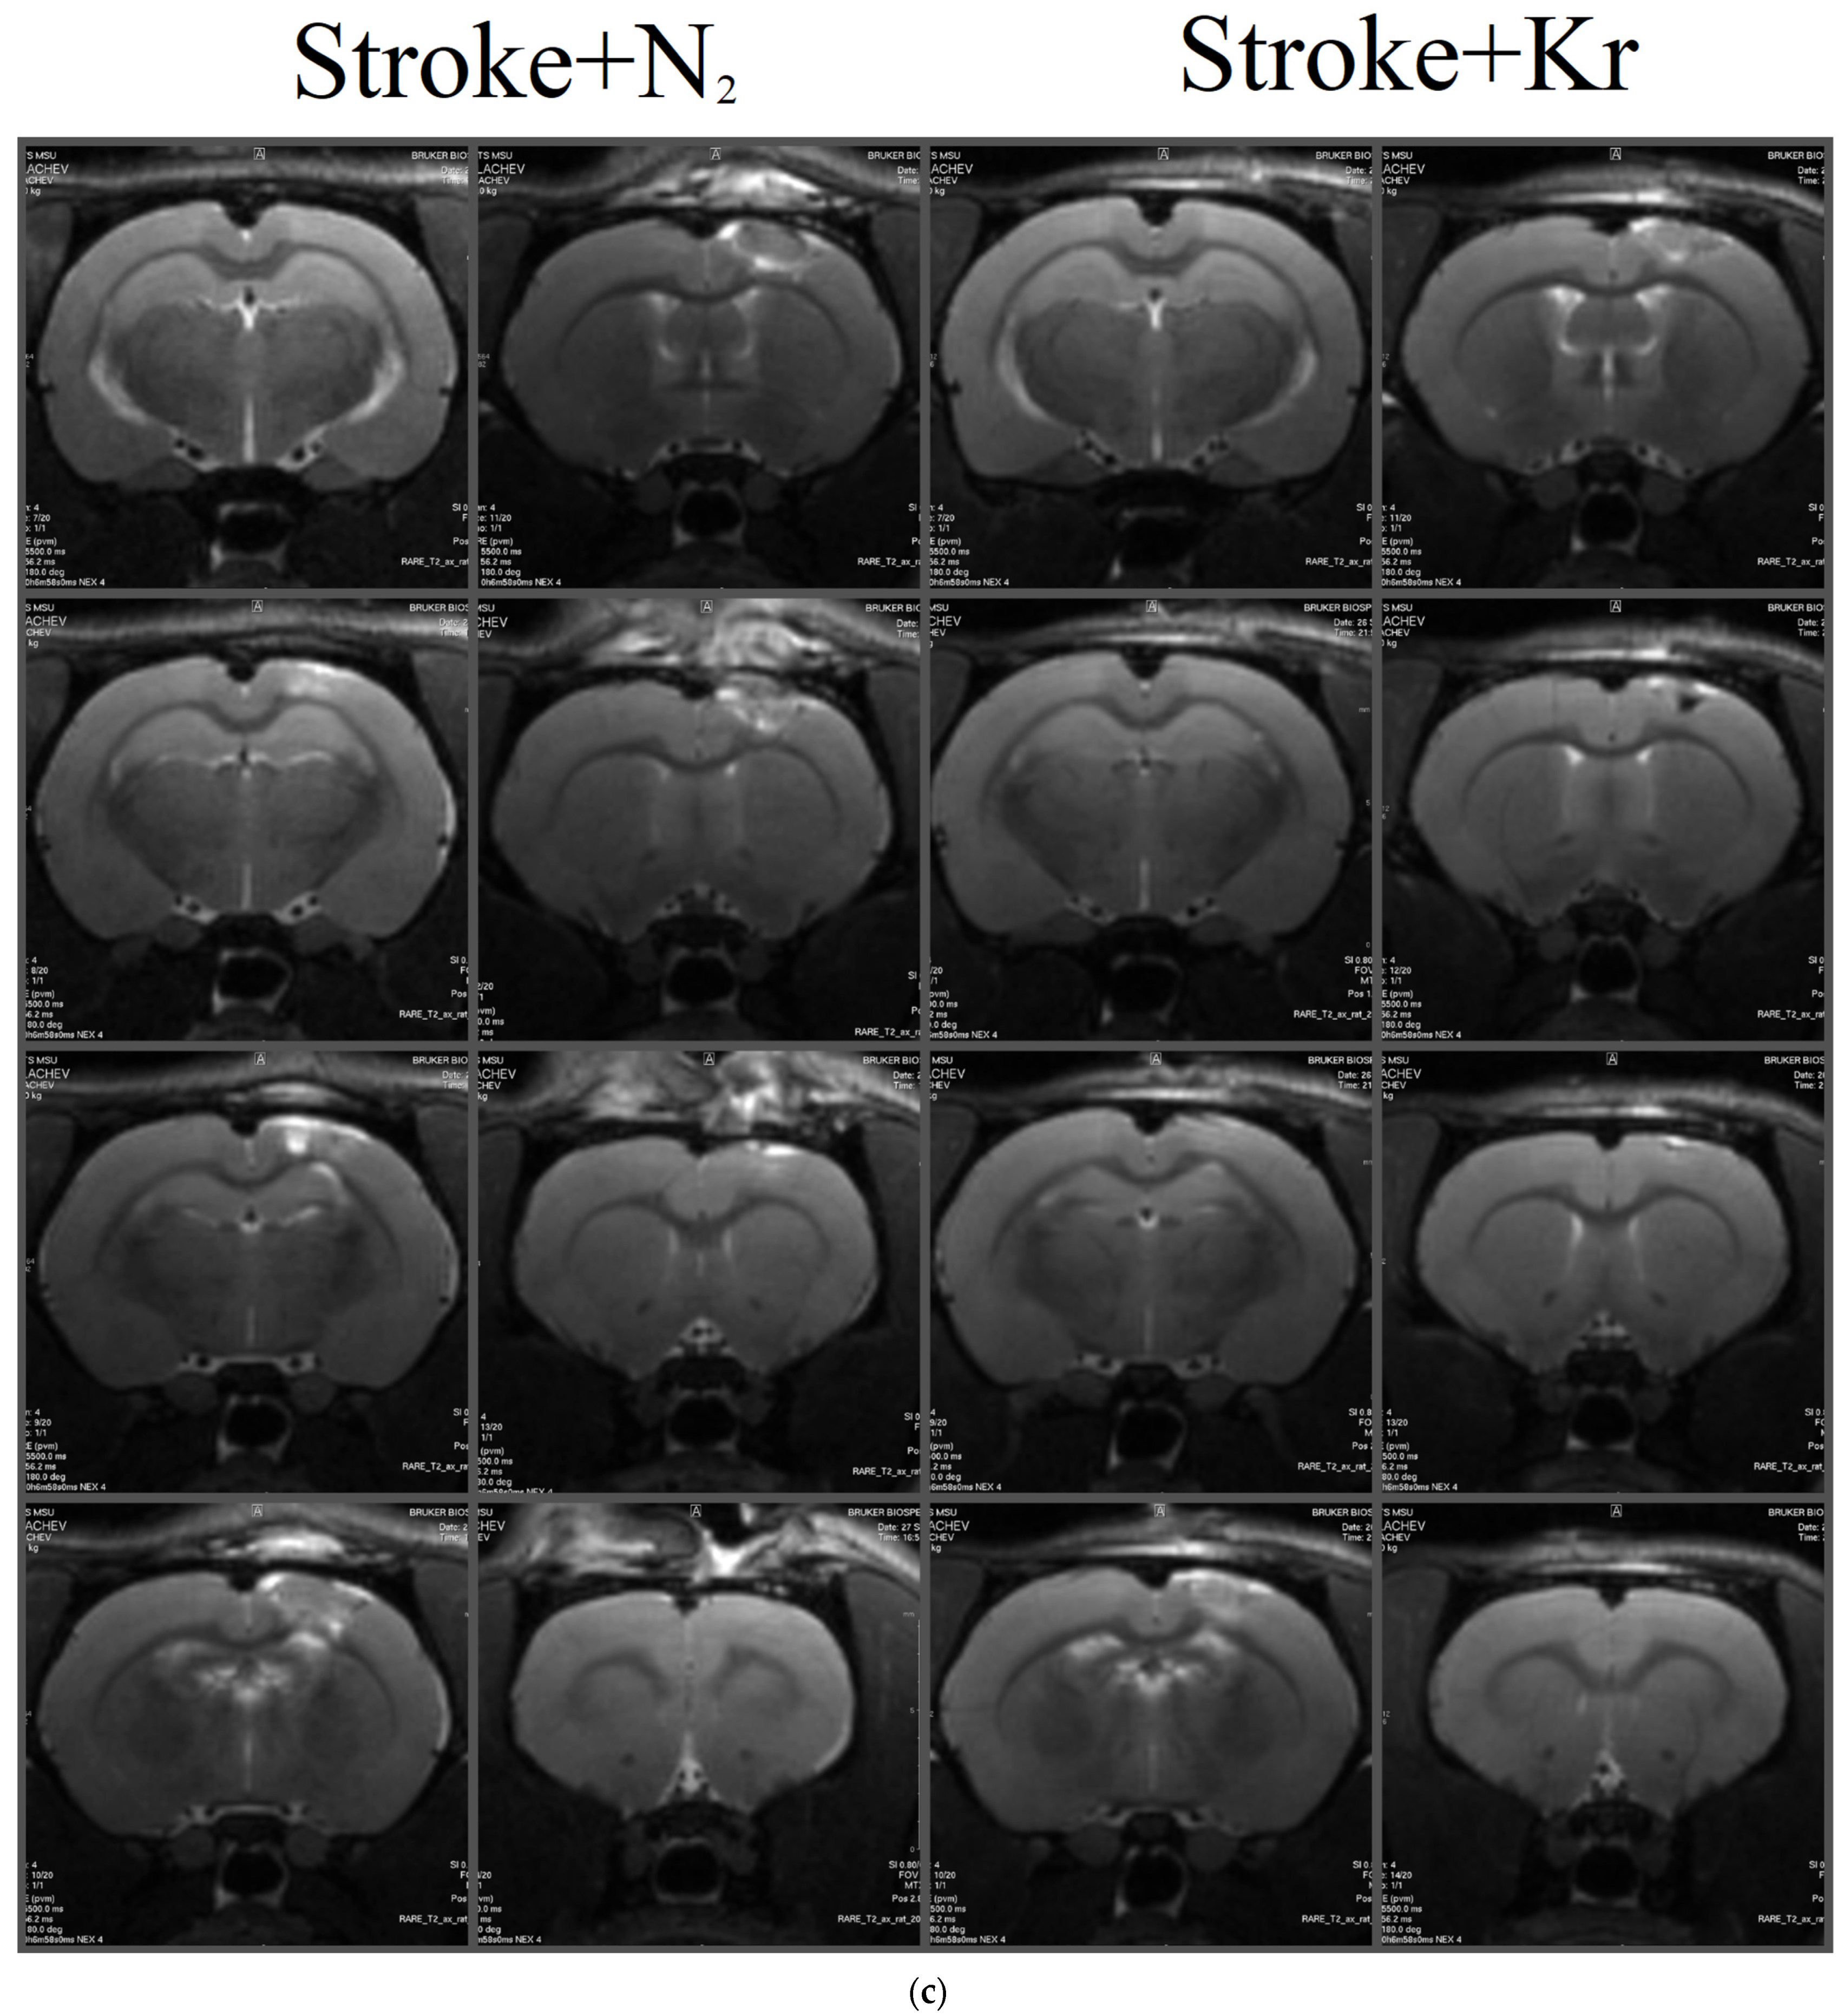

3.1. Krypton Protects Rat Brains Exposed to PIS

3.2. Krypton Inhibits Neuroinflammation and Cell Death after Ischemic Stroke